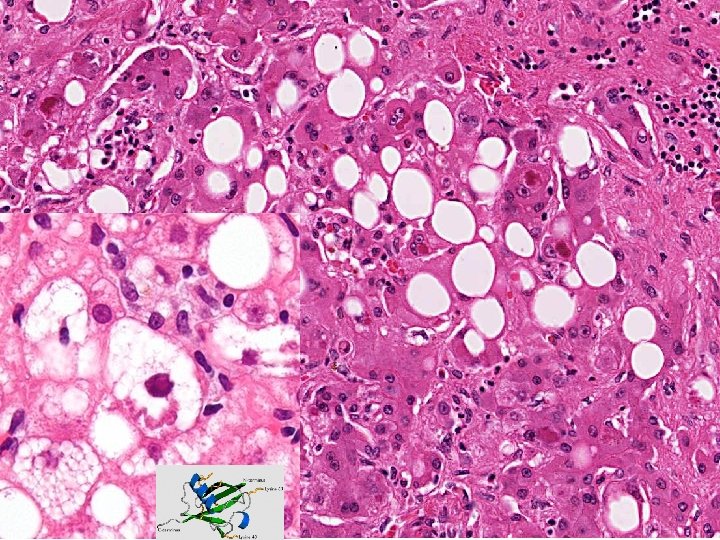

n Alcohol and the Liver Fatty Change n n n Alcohol hepatitis n n n present in over 90% of binge and chronic drinkers liver is enlarged but patient is asymptomatic changes are reversible with cessation of drinking macrosteatosis w/o inflammation or necrosis only between 10 - 15% of alcoholics will develop alcoholic hepatitis may have systemic symptoms and jaundice hepatocellular necrosis with Mallory bodies and PMNs (central hyaline sclerosis) thought to be a precursor of cirrhosis probably more than HALF will go onto cirrhosis if ETOH is not stopped Alcoholic cirrhosis n shrunken nodular liver with uniform small nodules (micronodular cirrhosis)

Fatty Change Biochemistry Catabolism of fat by peripheral tissues is increased, and there is increased delivery of free fatty acids to the liver n An excess of NADH over NAD stimulates lipid biosynthesis n Oxidation of fatty acids by mitochondria is decreased n Acetaldehyde forms adducts with tubulin and impairs function of microtubules, resulting in decreased transport of lipoproteins from the liver n